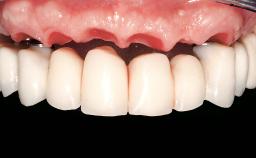

Conventional Loading of Eight Implants in the Maxilla and Final Restoration with a Full-Arch Gold-Ceramic FDP

A 35-year-old Caucasian female presenting with advanced periodontal disease involving both the maxillary and the mandibular dentition was referred for evaluation. The patient, a non-smoker in good general health, requested treatment for recurrent periodontal abscesses, tooth mobility, and discomfort during chewing, as well as restoration of her missing teeth with a fixed prosthesis to improve mastication and esthetics. All residual maxillary teeth exhibited plaque deposits, deep pockets, bleeding on probing, and class III mobility and were evaluated as hopeless. All residual mandibular teeth except tooth 37 could be maintained after periodontal therapy.

Prosthesis Type FDP

Defining Characteristics Fully edentulous upper jaw to be rehabilitated with an implant-borne fixed dental prosthesis